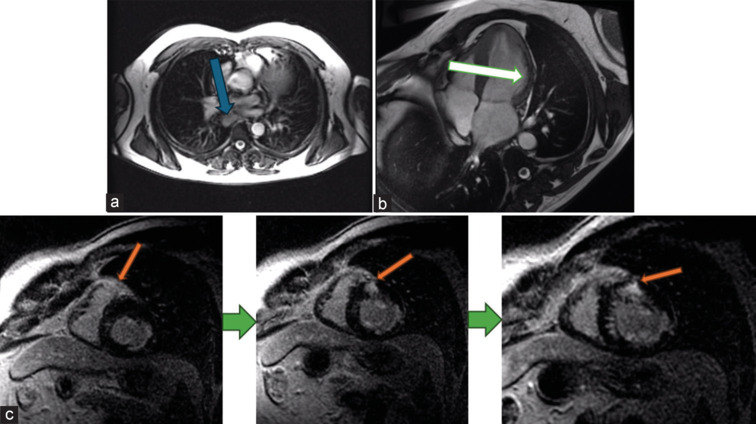

Cardiac sarcoidosis is an insidious condition with a highly variable clinical presentation that often mimics other diseases. Its diagnosis is particularly challenging, requiring a high index of suspicion and a comprehensive approach. Multimodality imaging plays a critical role in differentiating it from other conditions. We present a patient with cardiac sarcoidosis who also had concomitant coronary artery disease and colon cancer. The optimal therapeutic strategy for cardiac sarcoidosis remains uncertain. However, late gadolinium enhancement, a robust predictor of arrhythmic risk is crucial in guiding treatment decisions. This case report illustrates the risk of oversimplifying complex clinical scenarios by attributing signs and symptoms to a single disease, particularly in young, otherwise apparently healthy individuals. In such cases, clinicians must include rare diseases in their differential diagnosis.